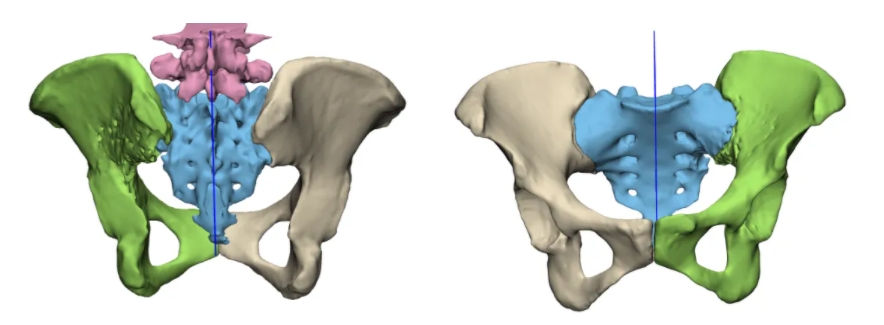

面对这一复杂病情,骨科肿瘤团队进行了综合评估,决定为患者实施左骨盆肿瘤 + 左侧骶骨肿瘤瘤体完整切除 + 3D 打印肿瘤假体置换手术。3D 打印肿瘤假体可量体裁衣,个体化重建肿瘤切除后的骨缺损,其微孔结构能实现假体与自体骨骨性愈合,提高长期稳定性,延长使用时间,这样不仅为患者成功保肢,还最大可能地保留肢体功能。